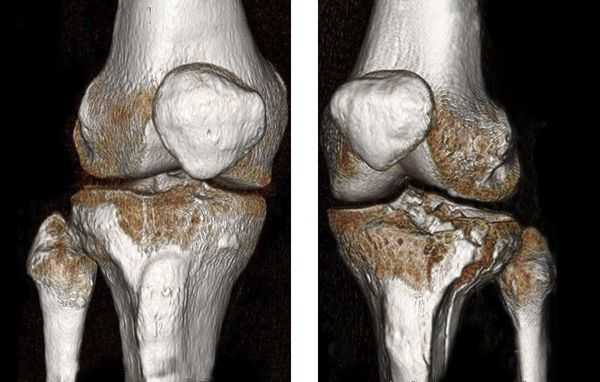

В некоторых случаях, если требуется детальная диагностика нескольких сегментов голени или пациент находится в тяжёлом состоянии, показана компьютерная томография с 3d-реконструкцией кости. Исследование можно проводить и при вынужденном положении конечности, но такой томограф есть не во всех клиниках. Поэтому в некоторых случаях, если информации недостаточно, делаются уточняющие прицельные рентгеновские снимки отдельных сегментов кости.

![Компьютерная томография голени]()

Перелом со смещением

Перелом со смещением - это нарушение целостности кости, при котором отломки утрачивают свое правильное положение и смещаются относительно друг друга. Проявляется деформацией и/или укорочением, реже - удлинением конечности. Существуют различные виды смещения, в том числе - по оси, по длине, ротационное и угловое. Диагноз подтверждают при помощи рентгенографии, при необходимости используют КТ, МРТ, артроскопию и другие исследования. Для устранения смещения проводят одномоментную репозицию, накладывают скелетное вытяжение или применяют различные оперативные методики.

- Переломы от сжатия или сдавления. Образуются при воздействии на кость в поперечном или продольном направлении. Трубчатые кости чаще повреждаются при сдавлении в поперечном направлении, при этом линия излома обычно проходит между диафизом и метафизом, более узкий диафиз внедряется в метафиз, а метафиз и эпифиз сплющиваются. В ряде случаев такие переломы не сопровождаются выраженным смещением, однако возможно и грубое нарушение взаиморасположения отломков вплоть до раздробления и полной утраты конгруэнтности суставных поверхностей.

- Эпифизарные (внутрисуставные). Обычно возникают в результате непрямого воздействия, например, скручивания конечности в сочетании с одновременным движением в суставе. Часто сопровождаются значительным смещением суставных концов и нарушением конфигурации сустава. Возможно сочетание с вывихом. В ряде случаев наблюдается стойкое ограничение подвижности в отдаленном периоде. Разновидностью эпифизарных переломов является эпифизеолиз - отрыв эпифиза в области хрящевой прослойки (зоны роста) у детей. Нарушение конфигурации суставных поверхностей при эпифизеолизах отсутствует, может наблюдаться угловое смещение.